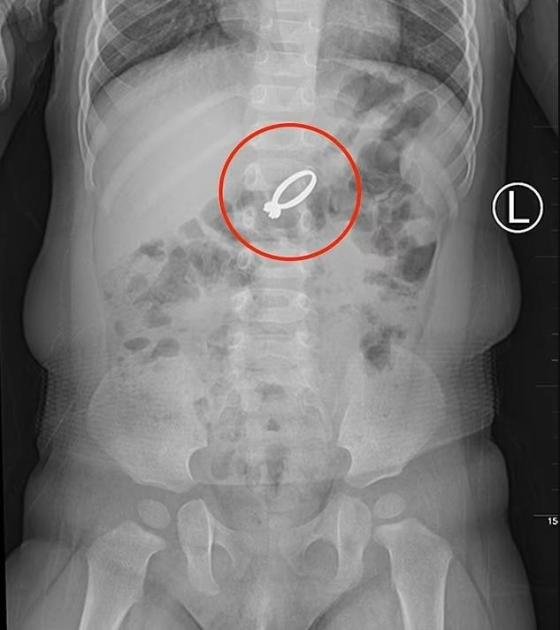

إنقاذ رضيعة صينية ابتلعت خاتماً ماسياً

إعداد: محمد عزالدين خضعت رضيعة صينية تبلغ من العمر 15 شهراً، إلى عملية جراحية تحت التخدير العام، لإخراج خاتم زواج…